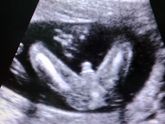

Была сегодня на УЗИ. А отправили со словами- врач хочет посмотреть живой или нет у тебя плод.

Я не переживала по поводу этих слов, потому что все утро меня пинали изнутри.

И не зря сходила. У нас будет сын! Максим.